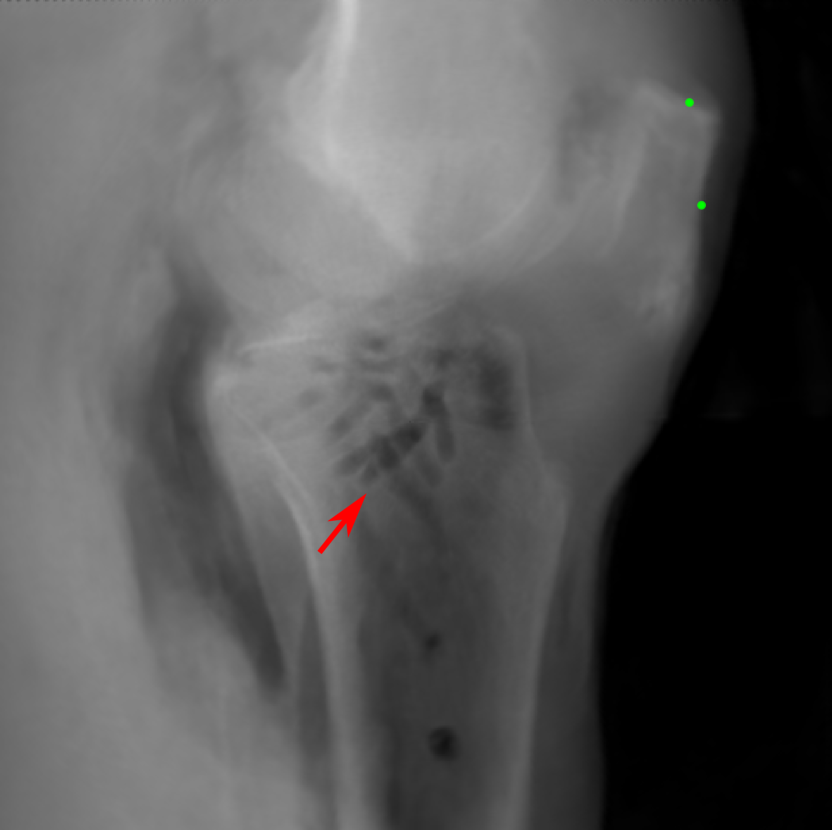

The complementary view setting for learning perspective deformation is also evaluated on real CBCT projection data. In this evaluation, real CBCT projection data from a dataset of knees with metal implants is used for testing, while DRRs created from volumetric CT datasets with inserted metals is used for training. Three exemplary DRR perspective projection images for training are displayed in Fig. 13, in which synthetic metal implants are inserted [34]. The appearance, e.g., image contrast and metal image resolution, of such DRR training images is different from that of real projection images in Fig. 14. In Fig. 14, the results for three knees, with and without metal implants, are displayed. The first and second rows are the 0superscript00^{\circ} and 180superscript180180^{\circ} perspective projections, respectively, rebinned to the virtual detector with geometric calibration based on their respective principal points and projections of the world origin. The third row displays their difference images, where the magnitude of deviation increases from the center towards the outside like it does in DRRs with an ideal scan trajectory (e.g., Fig. 6(e)), although real projection data suffer from various physical effects like beam hardening and Poisson noise. The fourth row displays the RGB stacks of 0superscript00^{\circ} and 180superscript180180^{\circ} perspective projection images. The magenta and green regions indicate structures with considerable perspective deformation, for example, the knee patella in Fig. 5.4, the top parts of the two metals in Fig. 5.4, and the bottom two screws in Fig. 5.4. The fifth row displays reference images, which are orthogonal projections of iterative reconstruction volumes from measured CBCT projection data. In the reference images, a total of five landmarks are selected, with the positions being marked by the green dots: In Fig. 5.4, two positions at the edges of the knee patella are marked; In Fig. 14(e) and Fig. 14(f), one position at the left edge of the fibula is marked for each image. In addition, a rectangular frame for the two metals is marked by the green dashed lines, while its width and height are indicated by the green solid lines, which are 29.71 mm and 111.99 mm, respectively. In Fig. 14(f), the centerlines of the bottom two screws are sketched by the green lines, which have the lengths of 17.14 mm (middle screw) and 19.38 mm (bottom screw). The corresponding rectangular frame for the two metals and the screw centerlines in the perspective projection images are marked as well, but in red color. In Fig. 14(a), the width and height of the metals are 32.56 mm and 109.85 mm, which have deviations of 2.84 mm and -1.95 mm to the reference ones, respectively. In Fig. 14(b), the centerline lengths are 18.91 mm and 19.54 mm, which have deviations of 1.77 mm and 0.16 mm, respectively. Although the bottom screw has little length deviation to the reference, the orientations of both screws are obviously deviated. The sixth row shows the results of Pix2pixGAN using 0superscript00^{\circ} and 180superscript180180^{\circ} polar inputs. For all of the landmarks, the green reference dots are all located accurately in the Pix2pixGAN images. The rectangular reference frame also accurately covers the metals in Fig. 14(g). In Fig. 14(h), although the two red centerlines do not exactly overlap with the green one, they are very close in lengths and orientations. Please zoom in for better visualization.

Refer to caption

(a) Real 0superscript00^{\circ} perspective

(b) DRR reference

(c) Pix2pixGAN

Figure 15: The enlarged ROIs containing the cavity structures to demonstrate differences in image resolution.

The region-of-interest covering the cavity/fracture structures indicated by the red arrow in Fig. 14 has been enlarged in Fig. 15 for better visualization of image resolution. In the real 0superscript00^{\circ} perspective projection ROI (Fig. 15(a)), the cavities and bone edges appear sharp. The presence of Poisson noise can also be visualized to some degree. In the DRR reference ROI (Fig. 15(b)), the cavities and bone edges appear blurry. This is likely caused by the partial volume effect in the intermediate 3D reconstruction volumes. In the Pix2pixGAN output (Fig. 15(c)), there is a slight smoothing effect. For example, the fine edge indicated by the arrow is blurred and the Poisson noise is reduced. But in general, image resolution is preserved for most anatomical structures, e.g., the cavities.

6 Limitations

(a) Reference

(b) Pix2pixGAN

(c) (b)-(a)

Figure 16: An exemplary phantom contains tiny beads, where false positive and false negative tiny beads are observed. (a) is the reference image, where five zoomed-in ROIs (No. 1-5) are displayed. (b) is the Pix2pixGAN prediction image (in Cartesian form) using two complementary views in polar coordinates, where the tiny beads in ROIs No. 1-4 are hardly visible (completely missing in ROIs No. 1 and 2, while blurred in the wrong locations in ROIs No. 3 and No. 4). The tiny bead in ROI 5 of (b) does not exist in the reference image (a). (c) is the difference image.

In the experiments on numerical bead phantom data, false positive and false negative beads are observed, especially for tiny beads. The results of an exemplary phantom containing tiny beads are displayed in Fig. 16. Fig. 16(a) is the reference image where five zoomed-in regions-of-interest (ROIs) (No. 1-5) are displayed. Fig. 16(b) is the prediction image (in Cartesian form) using two complementary views in polar coordinates. The tiny beads in ROIs No. 1-4 are hardly visible. The tiny beads in ROIs No. 1 and 2 are completely missing, which are false negative cases. The tiny beads in ROIs No. 3 and No. 4 are blurred with very low contrast, and they are in wrong locations. The tiny bead in ROI 5 of Fig. 16(b) does not exist in the reference image, which is a false positive case. After checking the corresponding polar image, we observe that the tiny beads are visible in the polar image despite of low contrast. Hence, the neural network is the main reason for the missing of tiny beads instead of resampling.

Reference

0superscript00^{\circ} perspective

(a) 18.16 0.6412

Pix2pixGAN

(b) 3.53 0.9595

Figure 17: An example of perspective deformation learning from the chest data. The ROIs in (a)-(c) are displayed in (d)-(f) respectively. The tiny metal implants in (d) and (e) are missing in (f).

For experiments on simulated anatomical data, similar to the results in the numerical bead phantom experiments (Fig. 16), tiny structures, which are around 1 mm in radius, cannot be reconstructed reliably, especially when such structures are not present in the training data. For example, the tiny metal implants in Fig. 17 and Fig. 17, probably vessel stents, are hardly visible in Fig. 17.

(a) 0superscript00^{\circ} perspective

(b) 0superscript00^{\circ} and 180180180 RGB

Figure 18: An example from the real cadaver data, where the Pix2pixGAN predicted metal rod is distorted (indicated by the red arrow) and certain K-wire shadows from perspective projection images remain (indicated by the blue arrows).

In the real cadaver data, certain metal implants are distorted in Pix2pixGAN predictions. For example, the long metal rod indicated by the red arrow is no longer straight in Fig. 18(c), although its position is between the corresponding magenta and green rods in Fig. 18(b). Another limitation is that certain structures like thin K-wires from 0superscript00^{\circ} and 180superscript180180^{\circ} perspective projection images will remain as shadows in the Pix2pixGAN prediction, for example, those indicated by the blue arrows in Fig. 18(c).